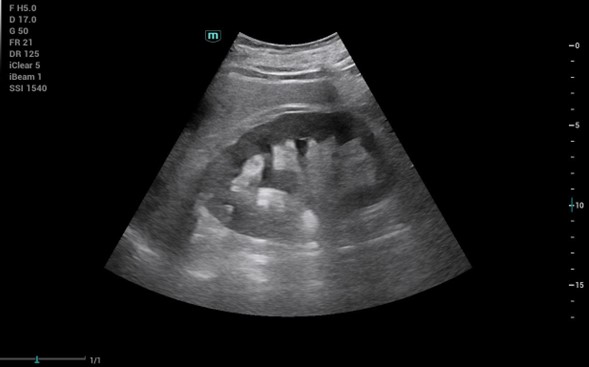

Manejo de cólico nefrítico con hidronefrosis grado II en hombre de 63 años y situación familiar compleja que impide manejo hospitalario.